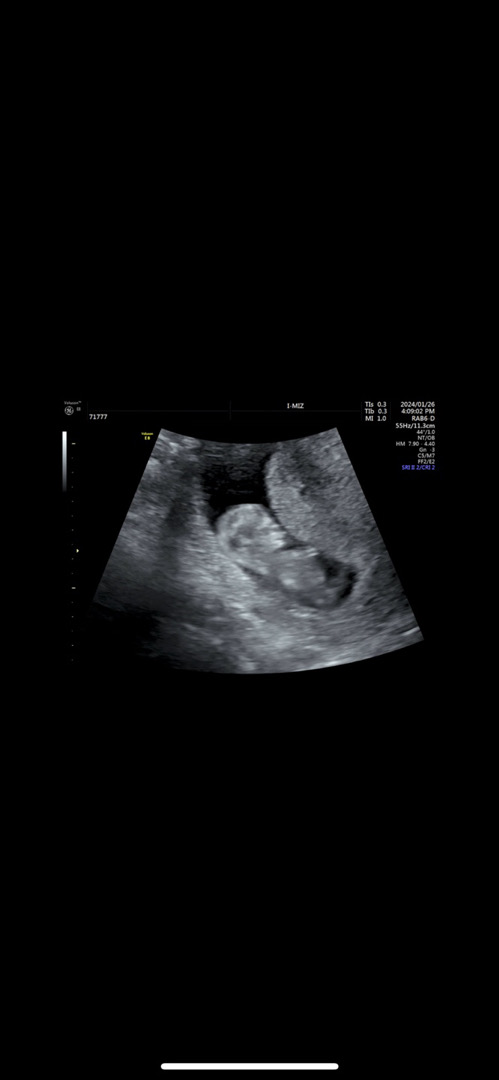

11주차입니다 아들 & 딸 어느 쪽 같아 보이시나요?ㅎㅎ 전 아무리 봐도 아직 잘 모르겟네요 각도법 잘 아시는 분들 한번 봐주세요~